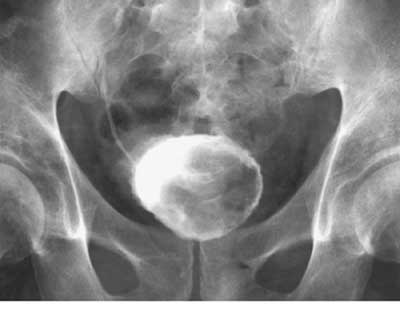

Figure 20-3

Figure 20-3. Image of the urinary bladder obtained on an intravenous urogram. The filling defect represents a papillary bladder cancer.